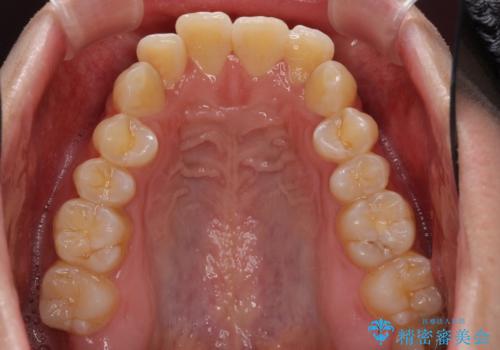

- 前歯のデコボコと若干口元が突出していることを気にして来院された患者様です。

全体的に軽微な叢生が認められ、口元もやや前方に突出していたため、インビザラインでのIPR(歯と歯の間を削る)と歯列全体の後方移動によって歯並びを整えることとしました。

上下ともに歯列の幅が狭かったため、側方に拡大することで前歯のデコボコや突出感を解消するためのスペースを獲得することができました。

歯並びが改善したことはもちろん、咬み合わせの改善まで実感することができ、患者様には大変満足していただけました。